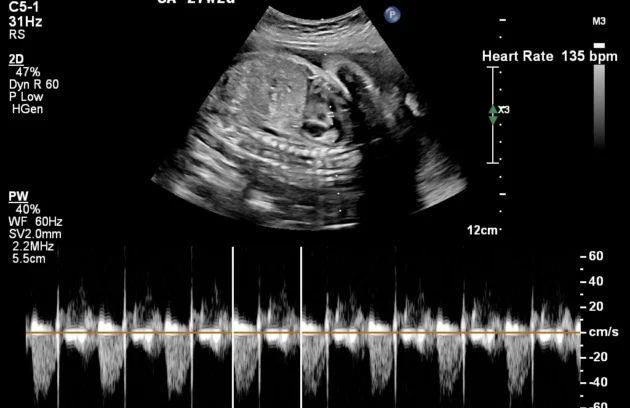

🔹 Fetal Echo / Adult Echo (Echocardiography)

Echo (Echocardiography) is a specialized ultrasound used to examine the heart. Fetal Echo evaluates the baby’s heart structure and function during pregnancy, while Adult Echo checks heart health in adults. It helps detect congenital heart defects, valve problems, and blood flow issues. If you need a fetal echo in Kathmandu, this test plays a vital role in early diagnosis and treatment planning.